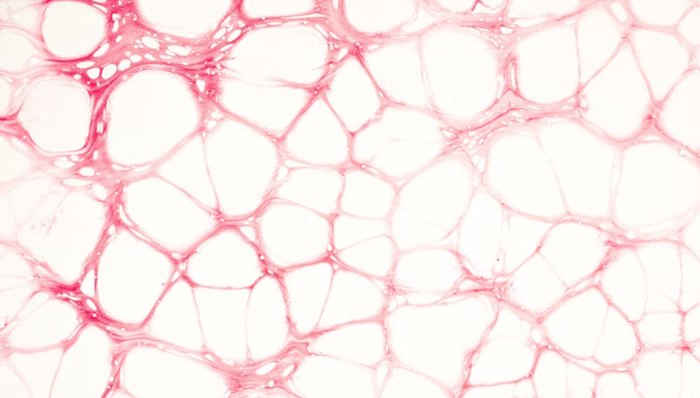

中重度钙化病变是导致经皮球囊血管成形术(PTCA)手术失败和血管急性闭塞的主要危险因素。特别是扭曲、成角、弥漫的严重钙化病变,手术风险较大,手术即刻的并发症以及早期和晚期支架内血栓的发生率较高。此前业内也有多种解决解决方案,主要是特种球囊和斑块修饰产品,但两大类产品都有其局限。

IVL的创新之处在于从肾结石治疗的冲击波技术汲取灵感,通过球囊导管把脉冲声压波输送至钙化部位把钙化的斑块“震松”,使血管恢复弹性及血流重塑病变血管的同时,避免了对血管内膜的损伤,因为冲击波能量只对硬的钙化病变有作用,而对于血管壁的正常结构无损伤。